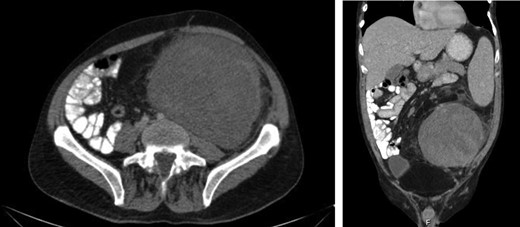

Laboratory work-up revealed a white blood cell count (WBC) of 1.0 K/ul, an absolute neutrophil count of 680, and an absolute lymphocyte count of 310. He was anemic with a hemoglobin of 6.9 g/dl. Rheumatoid factor was elevated to 180 IU/ml. An antinuclear antibody screen was positive at 1:320. Computed tomography (CT) of the abdomen and pelvis showed an enlarged spleen and a large heterogeneous mass in the left abdomen extending into the pelvis (Figs 1 and 2). A bone marrow biopsy showed abnormal CD3+ and CD8+ T-cell lymphocytosis with TCR(beta)+ and CD57+, consistent with the diagnosis of T-cell large granular lymphocytic leukemia.

Axial and coronal CT images demonstrates the large retroperitoneal mass (50 × 33 × 16 cm) displacing bowel, the left kidney, left iliac vessels and bladder to the right.

An enlarged spleen (16 × 10 × 22 cm) was identified on CT imaging obtained as part of the work-up of a palpable left abdominal mass.